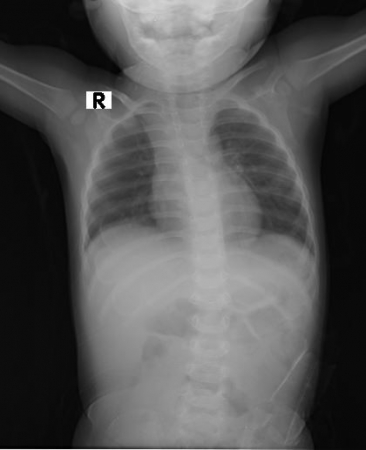

আমি একজন মেডিক্যাল টেকনোলজিষ্ট। তিতাস শিশু ও জেনারেল হসপিটালে কর্মরত আছি। রোগীদের সেবা করতে ভালবাসি। রোগ নির্ণয়ে এক্স রে,সিটি স্ক্যান,এম আর আই করে থাকি । রেডিয়েশনে মারাত্তক ঝুকি নিয়ে রোগীদের সেবা করছি। সবাই আমার জন্য দোয়া করবেন, যাতে সারা জীবন এভাবেই রোগীদের সেবা করতে পারি।

এটি শিশু রিহানের বুকের X RAY শিশুটি গুরুতর আহত অব্স্থায় আমাদের হসপিটালে ভর্তি । সবাই দোয়া করবেন শিশুটির জন্য ।